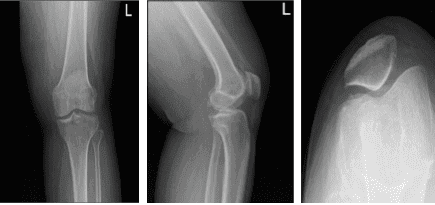

Left knee x-ray complete with patella

She had an X-ray result, we reviewed and discussed it. X-ray results showed normal radiographs considering her age, severity of pain, and inability to do activities of daily living and work, that’s the time we agreed to go with 3 tesla MRI of left knee to see the reason behind it. By this time, she will take tramadol until her next visit with an MRI result.